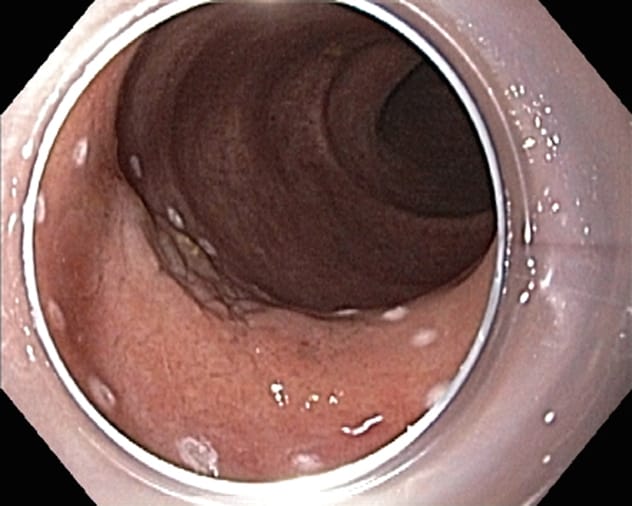

Large, biopsy-proven, flat dysplastic lesion marked by coagulation dots Large, biopsy-proven, flat dysplastic lesion marked by coagulation dots

Endoscopic submucosal dissection of a lesion Endoscopic submucosal dissection of a lesion

Post-endoscopic submucosal dissection defect Post-endoscopic submucosal dissection defect

Experienced endoscopists agree that patients with lesions larger than 2 cm and complex colorectal polyps should be referred to a high-volume, specialized center for endoscopic removal using EMR or ESD. Piecemeal removal of larger lesions is associated with an increased rate of recurrence up to 20 percent, and an incomplete first attempt is associated with an increased rate of failure of future endoscopic therapy. ESD can facilitate en bloc resection and reduce recurrence rates in patients with these larger, more-complex lesions.